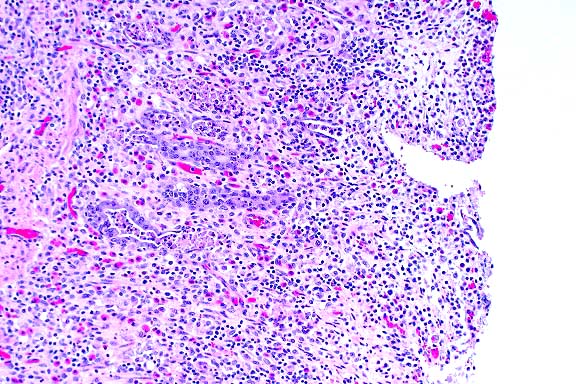

- Case 24-2. Lung. Alveolar septa are thickened by hypertrophic

type II pneumocytes, and alveoli are often filled with cellular

debris and rare multinucleate giant syncytial cells bearing bright

pink intranuclear and intracytoplasmic inclusions.